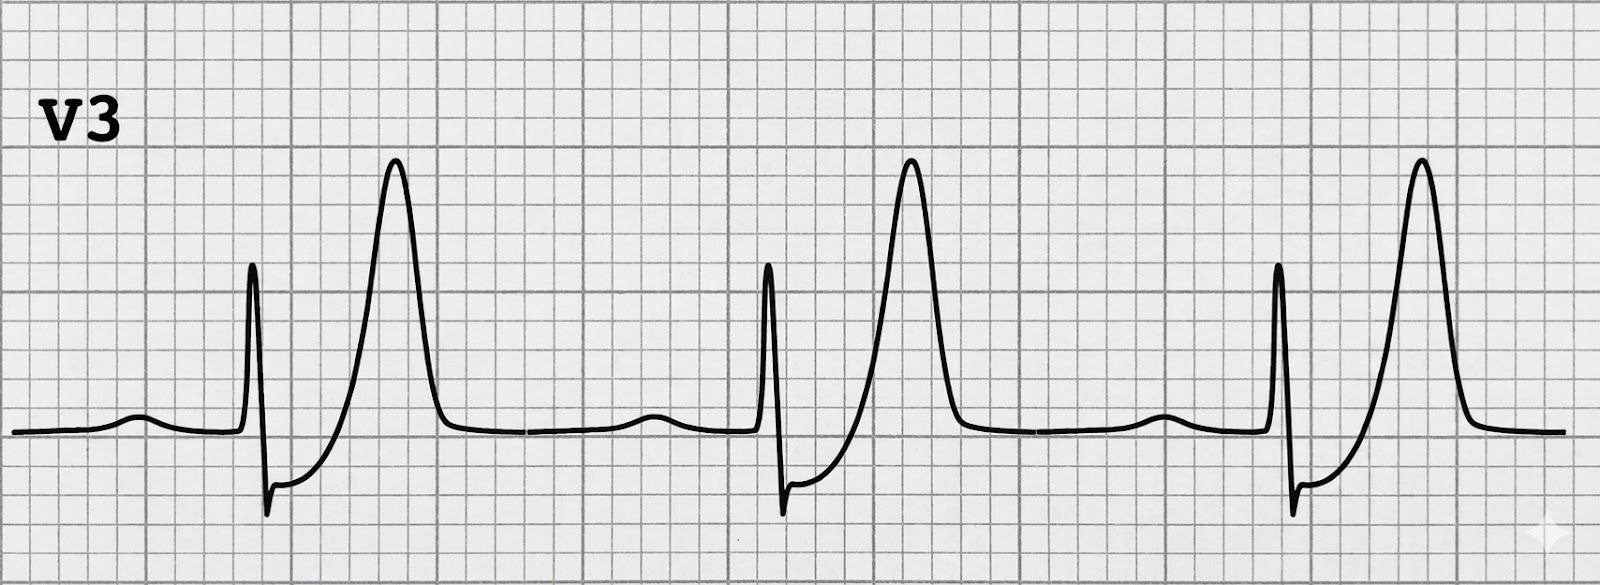

1. Sous-décalage ascendant du segment ST au point J (1 à 3 mm)

Le ST part du bas. Il remonte. C’est le premier signe — et c’est celui qui trompe, parce qu’un sous-décalage ascendant, en temps normal, c’est considéré comme bénin.

Sauf ici.

2. Ondes T hyperaiguës, hautes et symétriques en précordiales (V1 à V6)

Des ondes T géantes. Positives. Pointues. Symétriques. Dans toutes les précordiales. C’est le signe le plus visible — celui qui doit vous faire lever un sourcil.

3. Absence d’élévation du segment ST

C’est toute la perversité du pattern. Pas de sus-décalage. Pas de critère STEMI classique. L’algorithme de votre appareil ne va pas tirer la sonnette d’alarme. Votre protocole “STEMI oui/non” va répondre “non.”

Et pourtant, l’IVA est occluse.

Le pattern de De Winter est un piège parfait : pas de sus-décalage, troponine initiale parfois négative, interprétation automatique rassurante. Tout dit “ce n’est rien” — sauf les ondes T géantes qui crient “IVA occluse” si vous savez les entendre.